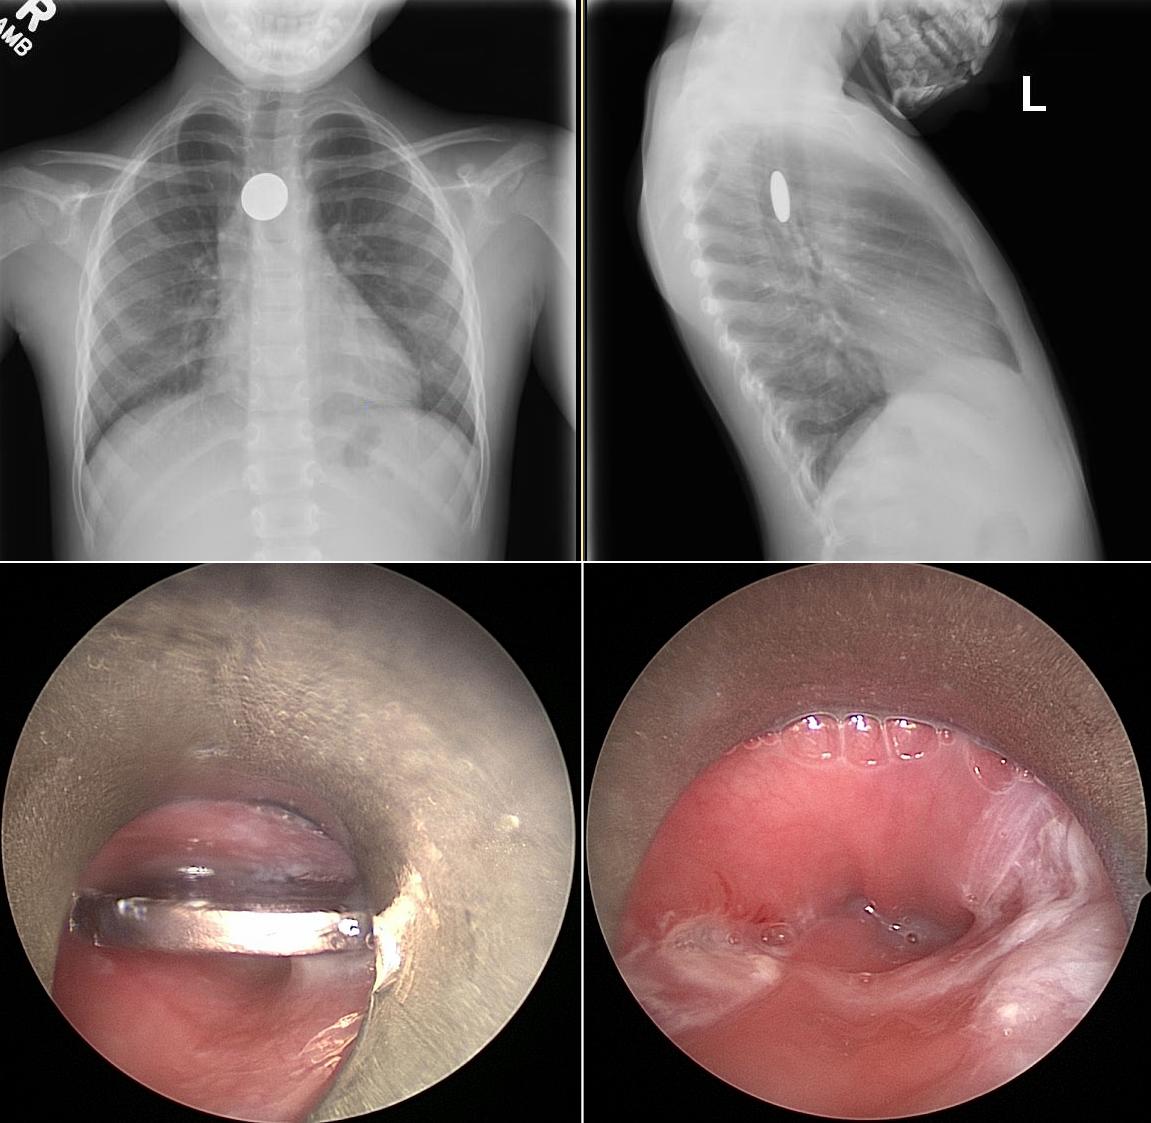

Esophagoscopy & Foreign Body Removal

Endoscopic removal of swallowed or stuck objects and diagnostic examination of the esophagus.